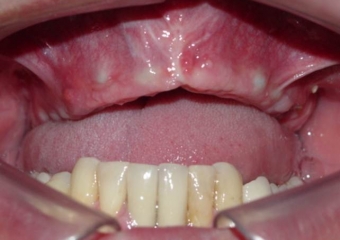

Prótese fixa em porcelana superior

Sorriso do caso terminado em abril de 2012